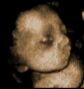

üç boyutlu ultrason

Üç boyutlu ultrason hakkında bilginiz var mı? Henüz çok yaygın olmayan bu teknoloji bebeğinizin daha ayrıntılı bir şekilde incelenmesine olanak sağlıyor. Çalışma prensibi basit: bebeğinizin çeşitli açılardan kesitlerini alıyor ve aldığı kesitlerin arasını önceden yüklü bir program yardımıyla kendisi dolduruyor ve ortaya yandakilere benzer görüntüler çıkıyor. Ancak gerçeğe yakın bir görüntü daha çok kesit alınması demek, bu da inceleme süresini belirgin şekilde artırabiliyor. Kesit sayısı az olduğunda ise ortaya çıkan görüntü gerçeğinden farklı olabilir. Şu an için gebelik takibinde üç boyutlu ultrasonografinin çok önemli bir yeri olmadığını söyleyebiliriz.